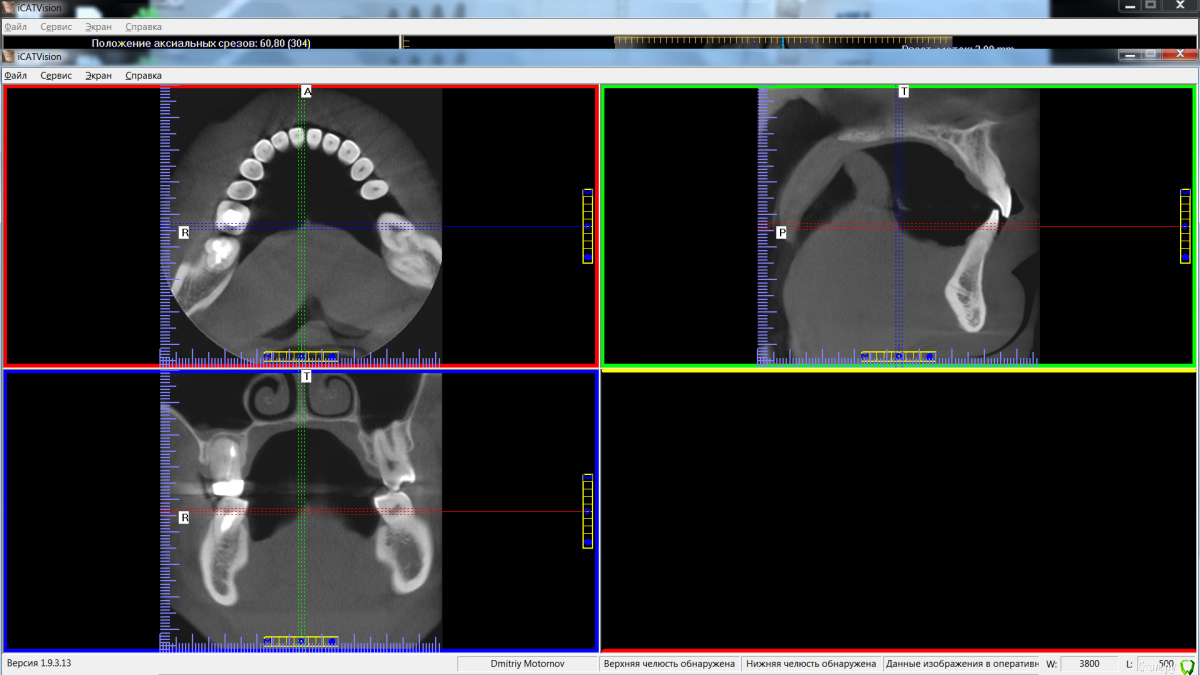

Maktub Опубликовано 13 августа, 2016 Автор Поделиться Опубликовано 13 августа, 2016 Сделал кт, дали диск с программой. Снимок оттуда выдирается или нет? Ссылка на комментарий

Maktub Опубликовано 14 августа, 2016 Автор Поделиться Опубликовано 14 августа, 2016 Не нашел, где там импорт снимка,сделал скриншот. Почему программа запускается только с диска, скопированная не работает? Ссылка на комментарий

Maktub Опубликовано 14 августа, 2016 Автор Поделиться Опубликовано 14 августа, 2016 вот Ссылка на комментарий